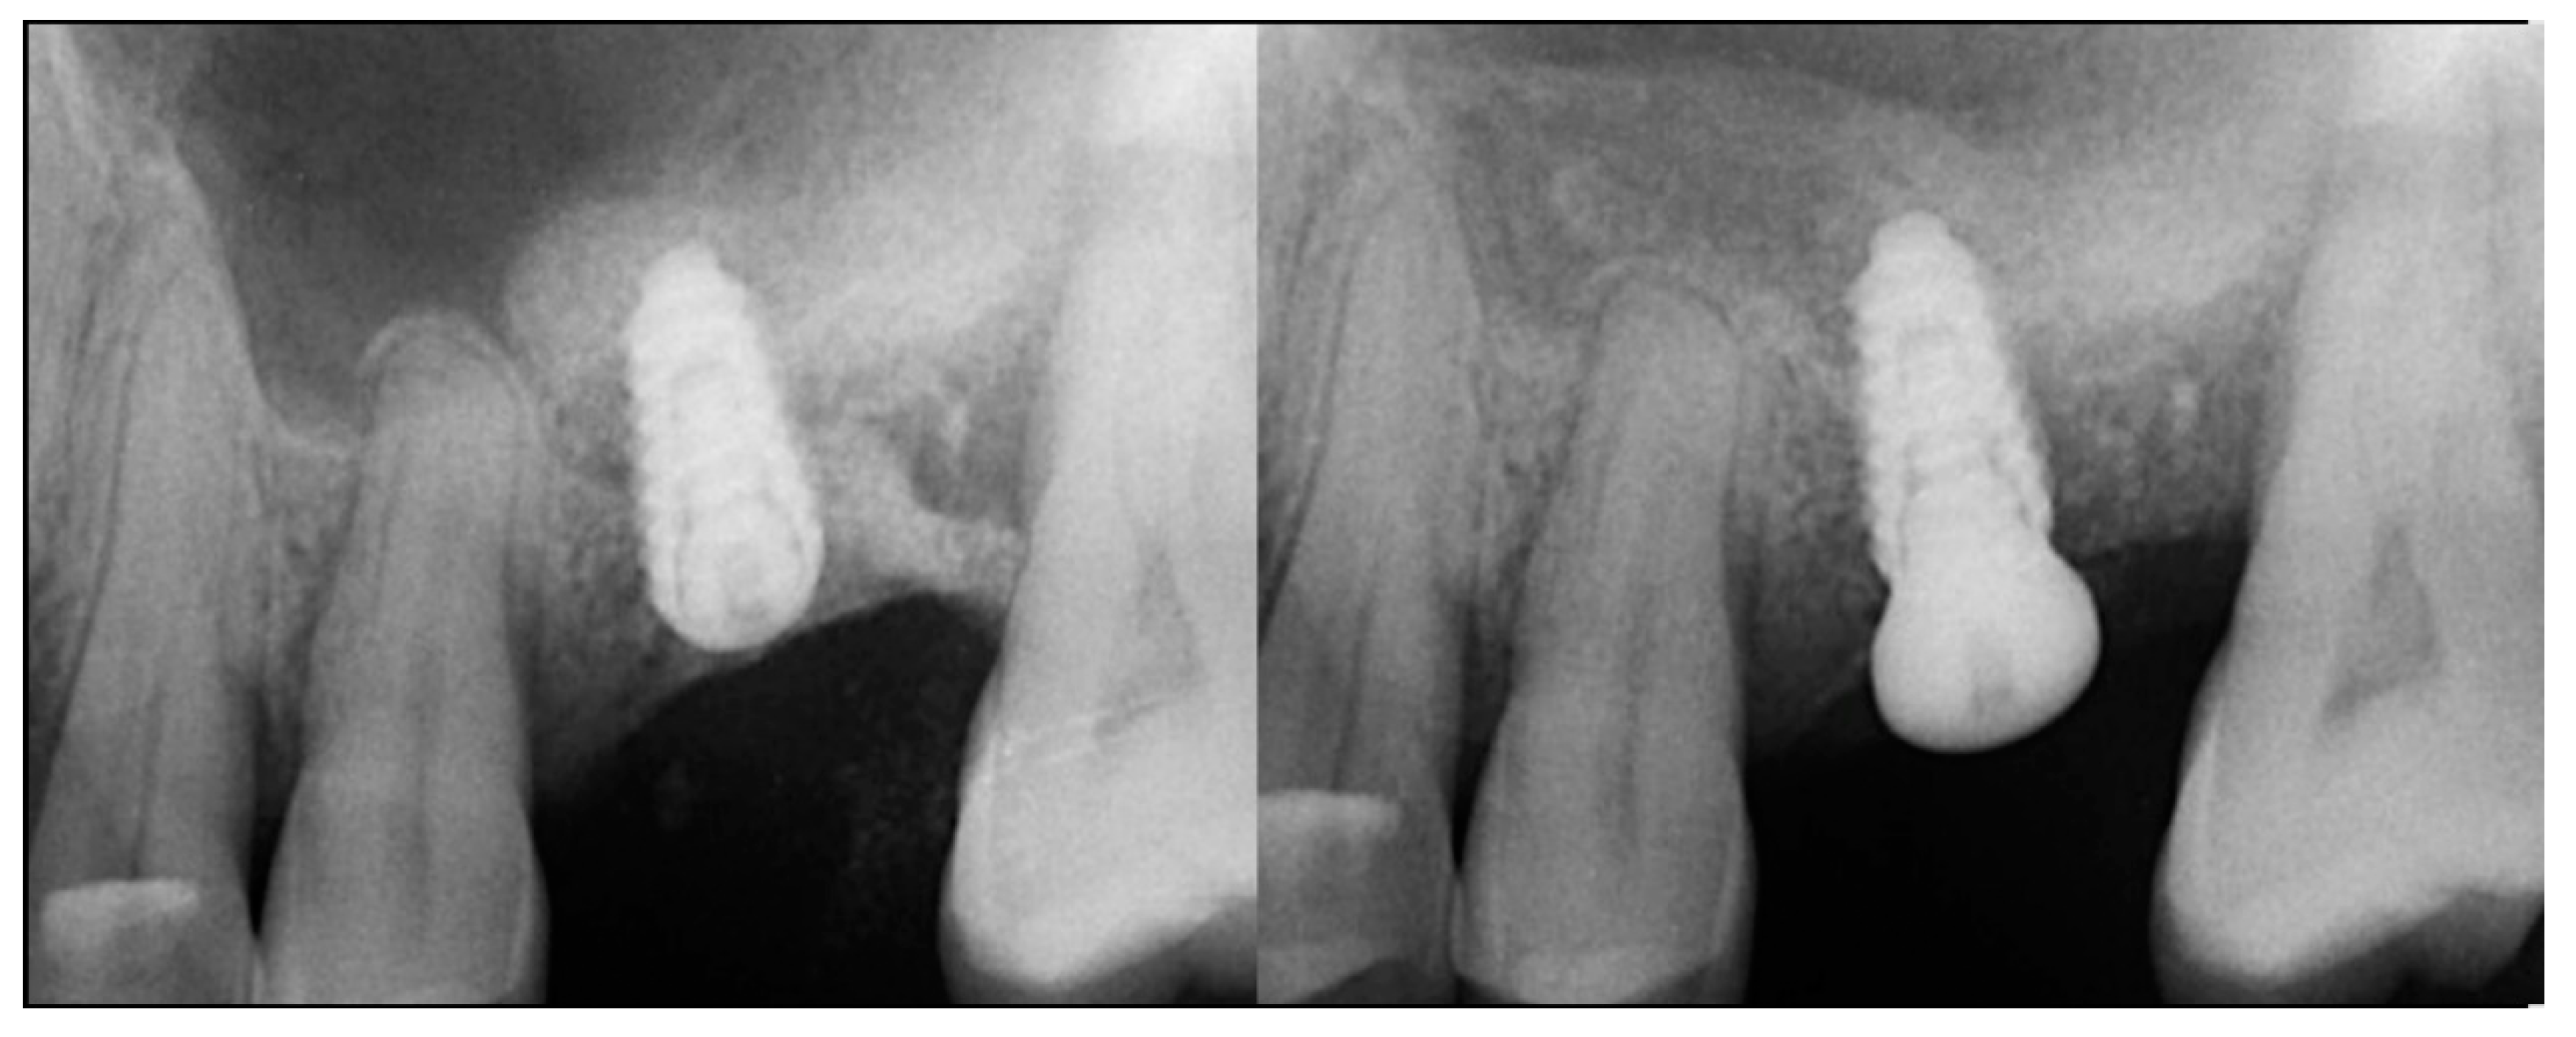

A 54-year-old female patient presented with loss of crowns on the upper left 1st and 2nd maxillary molars that had previous endodontic treatment. Examination noted minimal coronal tooth structure remaining and significant bone loss between the two molars with probing of over 10 mm. A periapical radiograph was obtained and confirmation of the poor condition of the two molars both structurally and periodontally was noted (Figure 1, left). Treatment options were discussed with the patient who wished a fixed approach. It was recommended that the two failing molars be extracted, and socket grafting be performed to create a crestal base to support an implant following site healing. At a subsequent surgery, a crestal sinus augmentation would be performed with simultaneous implant placement. This would then be allowed to heal before restoration of the implant at the 1st molar site was initiated.

Figure 1.

Failing endodontically treated 1st and 2nd molars (left), socket grafting with EthOss at time of extraction (middle) and following 10 weeks of healing demonstrating increased ridge height for implant placement with simultaneous crestal sinus augmentation (right).

The consent form was reviewed with the patient and then signed. Local anesthetic was administered into the buccal vestibule adjacent to the molars to be treated. The two molars were atraumatically extracted, and the sockets were curetted to remove any residual tissue. The EthOss graft material syringe was held vertically and per the manufacturer’s instructions, sterile saline was added to the syringe to wet the graft material. Once the saline had wetted the graft material, the end cap was removed from the syringe and a piece of dry gauze was utilized to remove any excess saline. The syringe was then carried to the intraoral site and expressed into the sockets. The material was gently compressed to shape it to fill the void being grafted with sterile gauze for 3 min at which stage it began to harden, showing resistance to pressure and being firm to touch. The flap margins were then closed to achieve primary closure and secured with 5–0 PGA sutured in an interrupted fashion. A periapical radiograph was obtained to document the socket grafting (Figure 1, middle).

The patient returned at 10 weeks post-surgery and a periapical radiograph was obtained to evaluate the graft healing (Figure 1, right). The graft was noted to have blended with the surrounding host bone and was deemed ready for implant placement. The soft tissue covering the grafted portion of the ridge was keratinized and no inflammation was noted (Figure 2). Local anesthetic was again administered in a similar manner as the previous surgery. A crestal incision was made from the distal of the distal papilla at the 2nd premolar to a point where the 1st molar would be positioned. A releasing incision was made at the distal of the papilla and also at the posterior extent of the crestal incision and extended into the buccal vestibule. A full-thickness flap was elevated to expose the crestal ridge (Figure 3). The graft had converted to bone at the extraction sockets. A pilot drill was utilized to start the osteotomy to a depth of 4 mm, 2 mm shy of the sinus floor as measured on the radiograph. The osteotomy was increased laterally utilizing Densah osseodensification burs (Versah, Jackson, MI, USA) to a width of 4 mm (Figure 4, left). EthOss graft material that had been hydrated in the syringe was dispensed into the osteotomy and the final Densah bur was utilized to elevate the sinus floor and laterally spread the graft material to gain height for the implant placement (Figure 4, right). A 5 mm × 8 mm Paltop Addvanced (Paltop, Cesarea, Israel) implant was introduced into the site to the desired crestal depth (Figure 5, left). A cover screw was placed, and additional EthOss graft material was placed at the crest to fill a depression on the distal aspect adjacent to the implant (Figure 5, middle). A periapical radiograph was obtained to document the implant and associated sinus/crestal grafting performed at this stage (Figure 5, right).